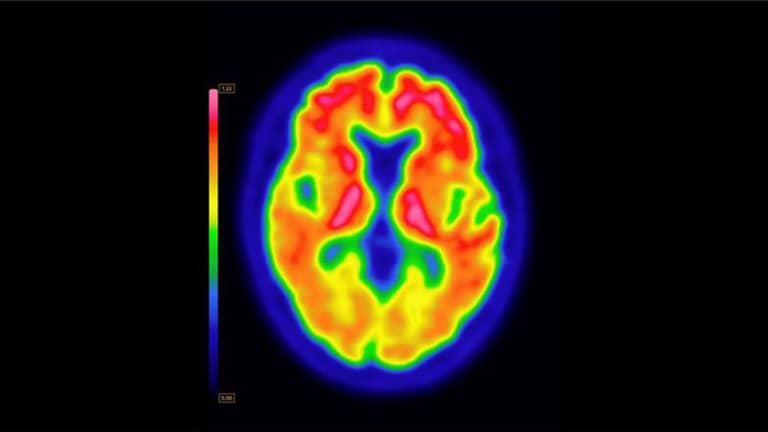

ووجد الباحثون أن إغلاق المسار العصبي داخل القشرة الجزيرية في المخ يمنع تطور الألم المزمن، بل ويعطل الشعور بالأوجاع في الحالات المرضية التي تشعر بآلام متواصلة.